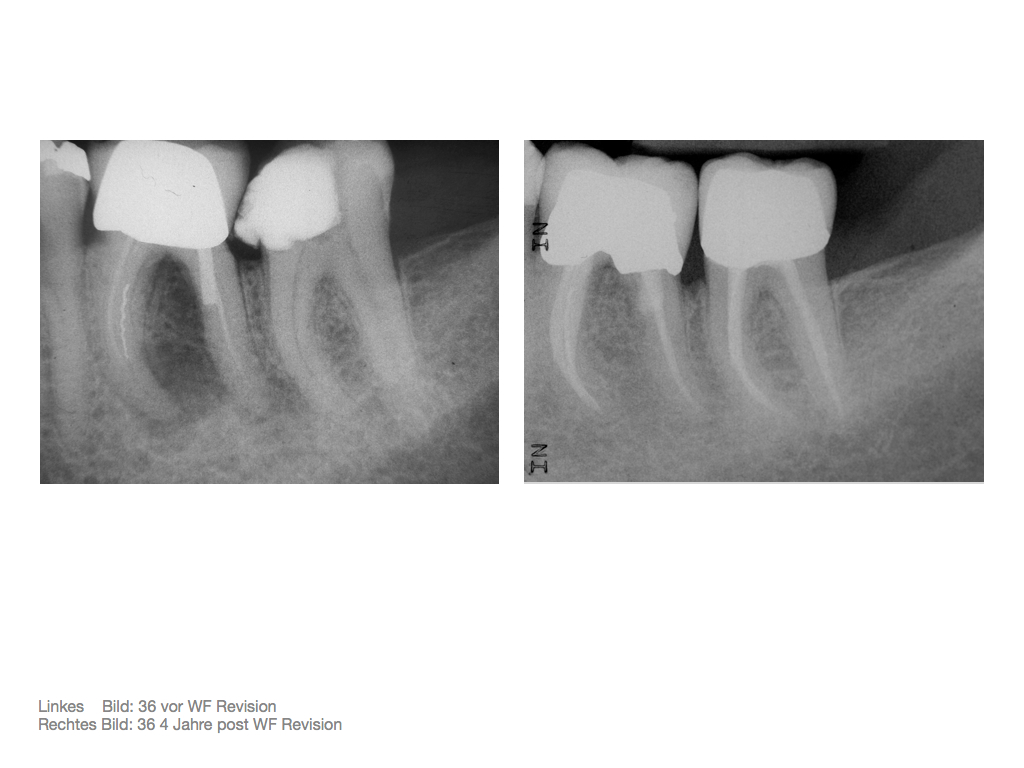

DMAWFR.015 Veröffentlicht 27. Februar 2012 am 1024 × 768 in Die Mutter aller WF – Revisionen – Recall nach 5,5 Jahren